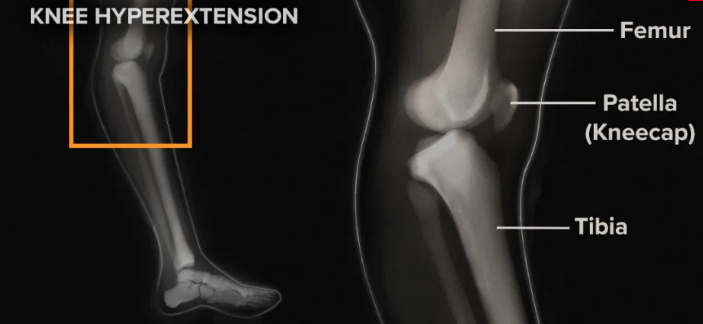

- 농구·배구처럼 빠른 방향 전환, 점프 착지 시 비틀림·과신전(hyperextension)에 의한 스트레스

- 체중이 실리는 상황에서 무릎이 과신전되거나, 무거운 물건을 들어올릴 때 발생